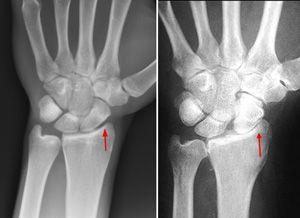

In this wrist with advanced rheumatoid arthritis, the alignment of the carpal bones has collapsed, leading to a loss of joint space between the bones.